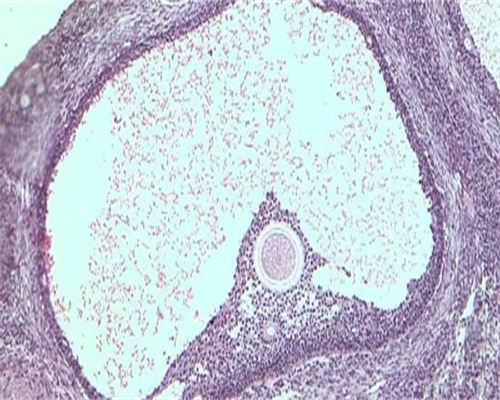

2、单卵双胎的形成

单卵双胎的形成则与上不同,是一个精子与一个卵子结合产生的一个受精卵。这个受精卵一分为二,形成两个胚胎。

由于他们出自同一个受精卵,接受完全一样的染色体和基因物质,因此他们性别相同,且就像一个模子里出来的,有时甚至连自己的父母都难以分辨。这种相似不仅外形相似,而且血型、智力、甚至某些生理特征,对疾病的易感性等都很一致。我们常说的连体婴儿,实际上就是这种单卵双胎,只是由于当初受精卵分裂时的不完全造成了某些部位相连。